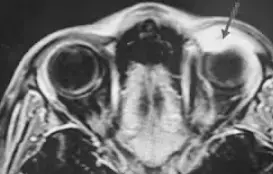

Рисунок 6. МРТ глазных орбит с контрастированием. На фоне проводимой терапии состояние без динамики, в связи с чем проведено дообследование: КТ орбит и МРТ орбит с контрастом. КТ показало образование левой орбиты, активно накапливающее контрастное вещество. МРТ орбит с контрастом — образование левой орбиты 2,6×1,5×2,9 см, активно накапливающее парамагнетик (см. рис. 6).

Пациент консультирован онкологом. Учитывая быстрый рост и локализацию, нельзя исключить саркому мягких тканей или лимфому. Из семейного анамнеза: у бабушки — рак груди, у прабабушки и прадедушки — рак гортани и легкого.